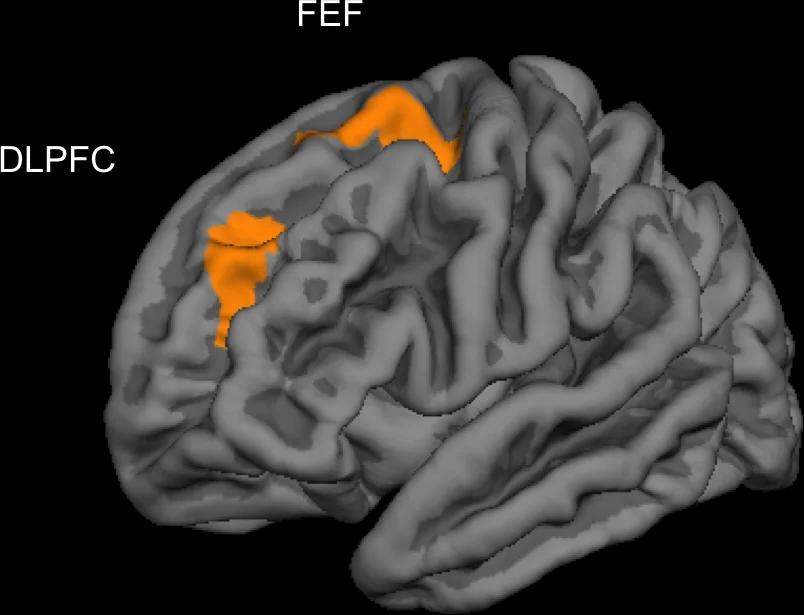

В эксперименте участвовали как юноши, так и девушки. С их слов они проводят за видеоиграми в среднем 12,6 часов в неделю (мужчины играют дольше женщин). Ученые заметили у игроков утолщение левой дорсолатеральной префронтальной коры головного мозга (DLPFC) и коры в зрительной области лобной доли слева (FEF) — в цитоархитектоническом поле Бродмана 8. При этом исследователи не обнаружили, что кора утончилась в какой-либо другой области.

Дорсолатеральная префронтальная кора связана с несколькими мыслительными функциями. Благодаря ей человек может думать о нескольких вещах одновременно и переключать вниманием с одной идеи на другую, в ней обрабатывается поступающая информация, она участвует в процессах принятия решений и стратегического планирования. Зрительная область лобной доли регулирует движения глаз и отвечает за внимание. Ученые отмечают, что все это требуется в видеоиграх.